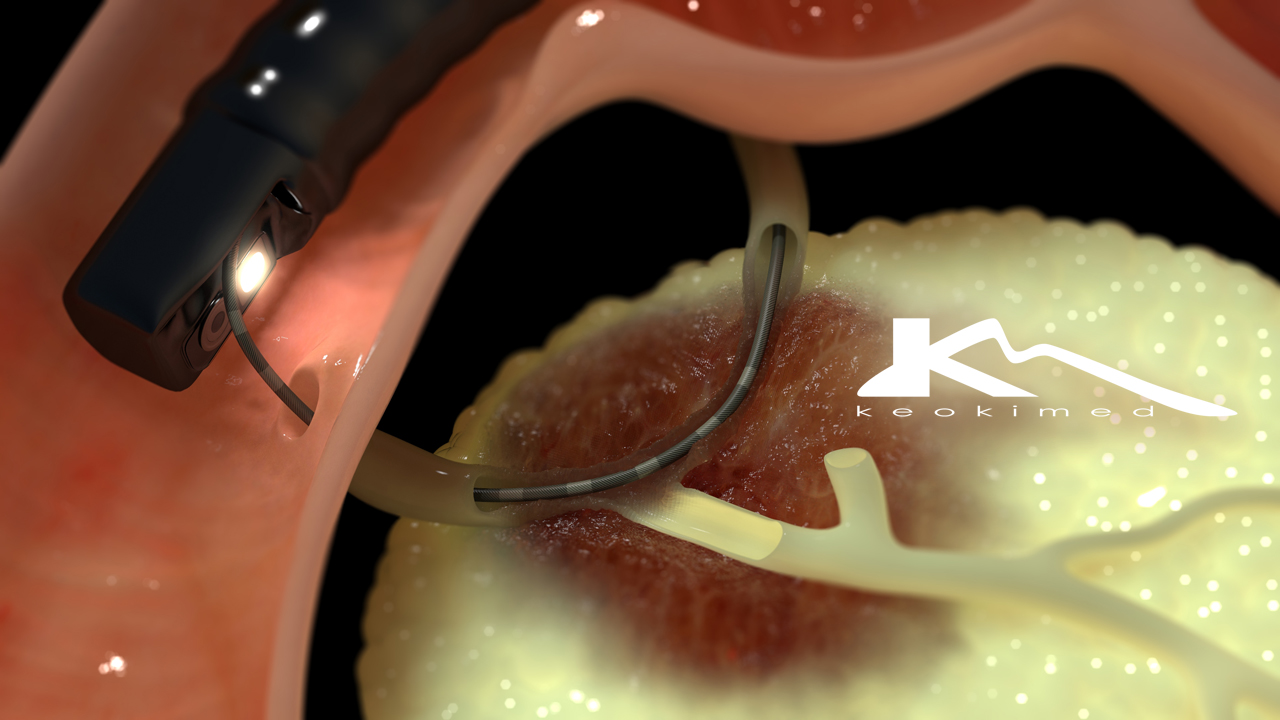

ERCP的做法

用一根类似于胃镜的镜子——十二指肠镜,在喉咙喷入局部*醉药麻**物及肌肉注射镇静止痛药物的情况下,患者保持清醒状态,采取俯卧位,十二指肠镜由口腔进入,经过咽、食管、胃到达十二指肠降段,此时可见十二指肠大乳头,这是胆汁及胰液进入肠道参加食物消化的重要关卡。

经十二指肠乳头导入专用器械进入胆管或胰管,在X线透视下注入造影剂显影进行诊断,并在诊断的基础上进行取石、引流等相应治疗。